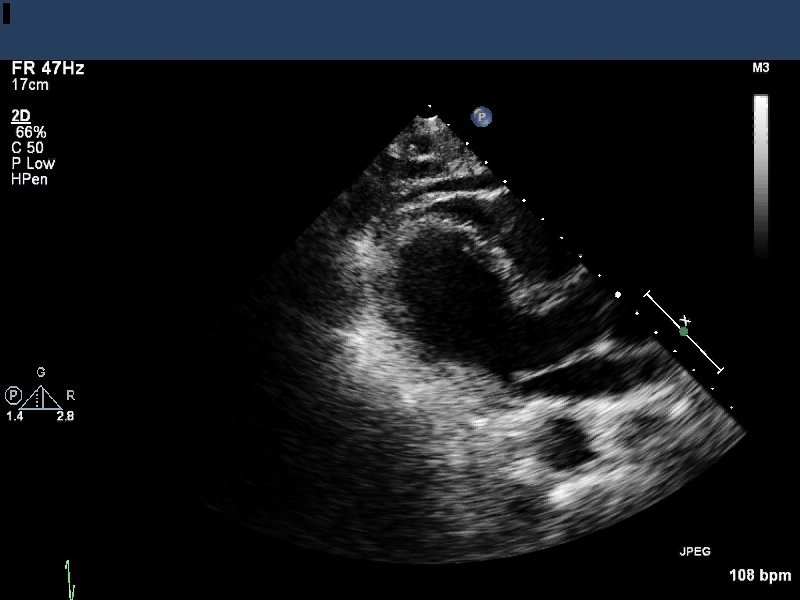

Image 1 is an apical 4-chamber view which shows apical ballooning and

hyperdynamic basal shortening, a classic depiction of takotsubo

cardiomyopathy. An abnormality is visualized in the left ventricular

apex.